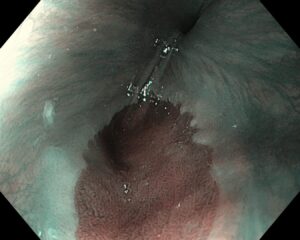

Атлас

В эндоскопическом атласе обычно представлены изображения и видео, полученные во время процедур, проводимых врачами-эндоскопистами. Эти изображения и видео могут использоваться для обучения студентов медицинских учебных заведений, повышения квалификации медицинских работников, а также для консультации врачей при диагностике и лечении различных заболеваний.